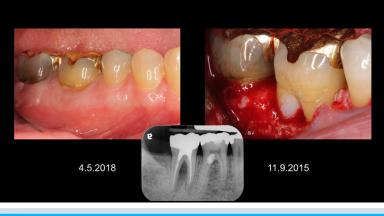

審美領域における外部歯根吸収への対応

歯根の外部吸収は外傷、過剰なルートプレーニング、ウォーキングブリーチなどによって引き起こされる。外部歯根吸収は外部表面吸収、外部炎症性吸収、外部置換吸収、外部歯頚部吸収に分類することができる。演者は自身の症例を通して、それぞれのタイプにおける歯根外部吸収への対応法について紹介している。